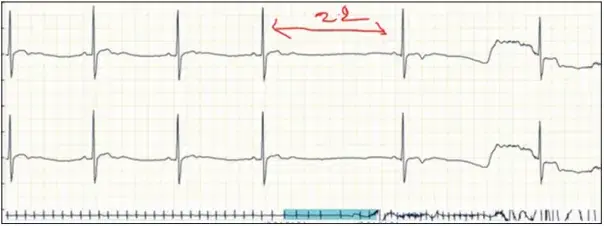

Figure 3: ECG graph with second degree AV block (Type 1).

Our study found five cases contributing to 4.58% of significant cardiac rhythm disorders. This consists of two cases of second-degree atrioventricular block (Type 1), two cases of atrial tachycardia, and one case of sinus pauses (two episodes). Second-degree AV block and atrial tachycardia cases were found in the age group of 21–30 years and sinus pauses were in the age group of 41–50 years. There were 11 cases of premature ventricular complexes, supraventricular premature complex couplets-4, and supraventricular premature complex-16 cases, but as the total burden was <10% in 24 h, it was considered insignificant. [Figures 3-5] depicts the ECG changes of the cardiac rhythm disorders.